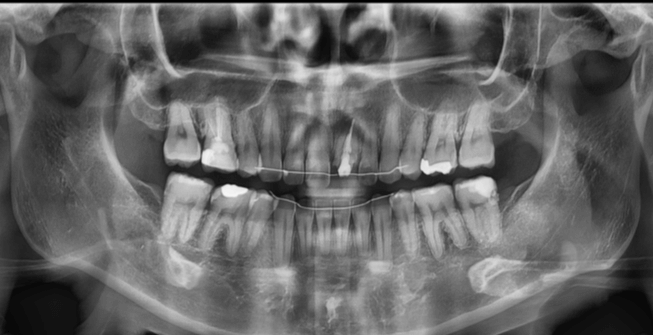

| 年齢・性別 | 22歳女性 |

|---|---|

| 主訴 | 上下顎前歯部に開咬と口元の突出感を気にされて来院された22歳女性。咬み合わせや審美的な改善を希望されていました。 |

| 治療期間・回数 | 3年9ヶ月・32回 |

| 費用 | 930,000円 |